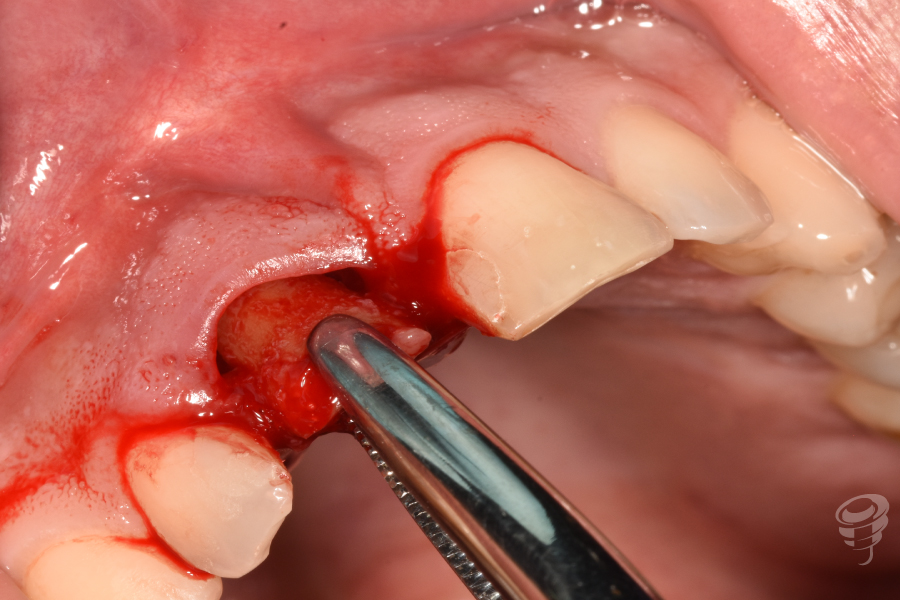

- Extracción atraumática del diente 11 con periotomos y luxadores.

Figura 5